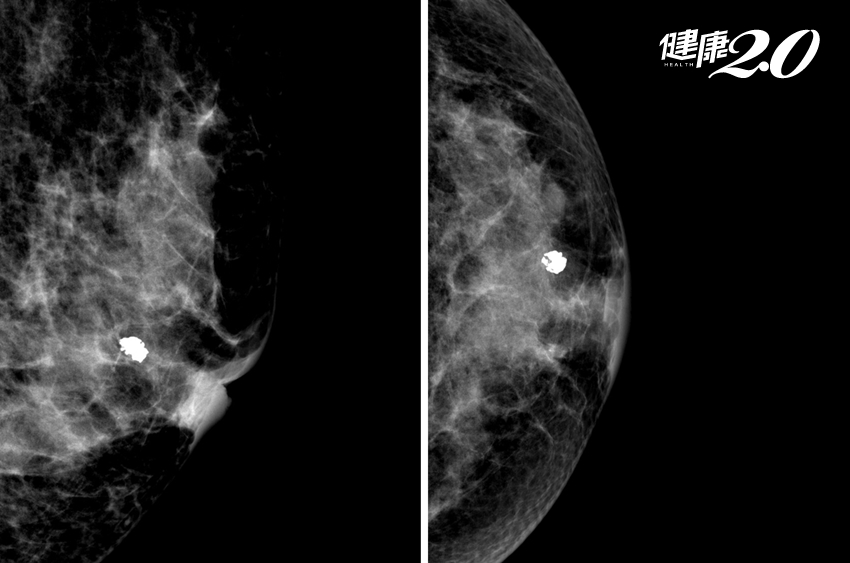

▲ 有惡性疑慮的鈣化點

2. 不規則外形,例如分岔狀、線形、 棒狀、多角形等。

3. 鈣化點周邊乳房組織密度有變化。